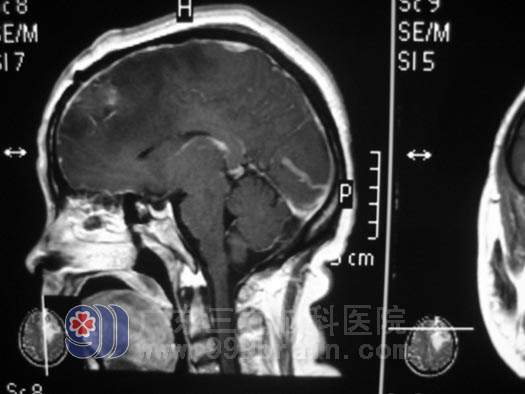

在广东三九脑科医院,神经外五科的鲁明主任为其做了详细的检查,头部MRI见双侧额叶、右侧丘脑占位!胸部CT见右侧肺部占位!腹部B超见肝右叶实质性占位!结合病史及影像学资料,钟阿姨全身多发性病变,考虑肺癌脑转移可能,左侧额叶病灶较大,水肿明显,压迫明显,病情紧急,在完善相关检查后立即安排了手术, 12月24日在全麻下行左侧额叶占位切除术,手术中见肿瘤质软,供血丰富,有出血及坏死,并见黄色囊液流出,肿瘤内侧紧贴大脑镰,在显微镜下对肿瘤进行全切,手术过程很顺利。第三天,钟阿姨已经可以下床活动了,术后病理结果为:转移性腺癌,免疫组化验检测结果提示癌组织源自肺。现在的她仍在行进一步的放射治疗中。

手术后